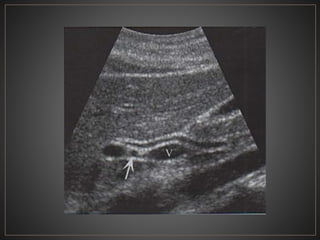

• #32 USG en escala de grises corte sagital, donde se observa el coledoco, anterior a la vena porta (v) y al conducto hepatico comun

• #52 USG en escala de grises donde se observa una dilatación de los conductos biliares intrahepaticos, con el signo del punteado central, a la aplicacion de doppler color se percibe flujo en las venas portales.